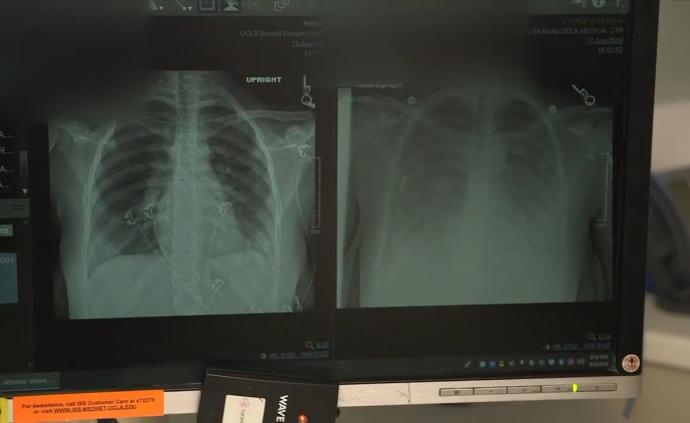

美國電子煙致病數(shù)據(jù):1299病例26死

當(dāng)?shù)貢r間10月10日,美國疾病控制與預(yù)防中心公布調(diào)查報告,全美49個州與地區(qū)共確診1299例因吸電子煙導(dǎo)致的致命肺病,其中26人死亡。死者年齡最小的僅17歲。